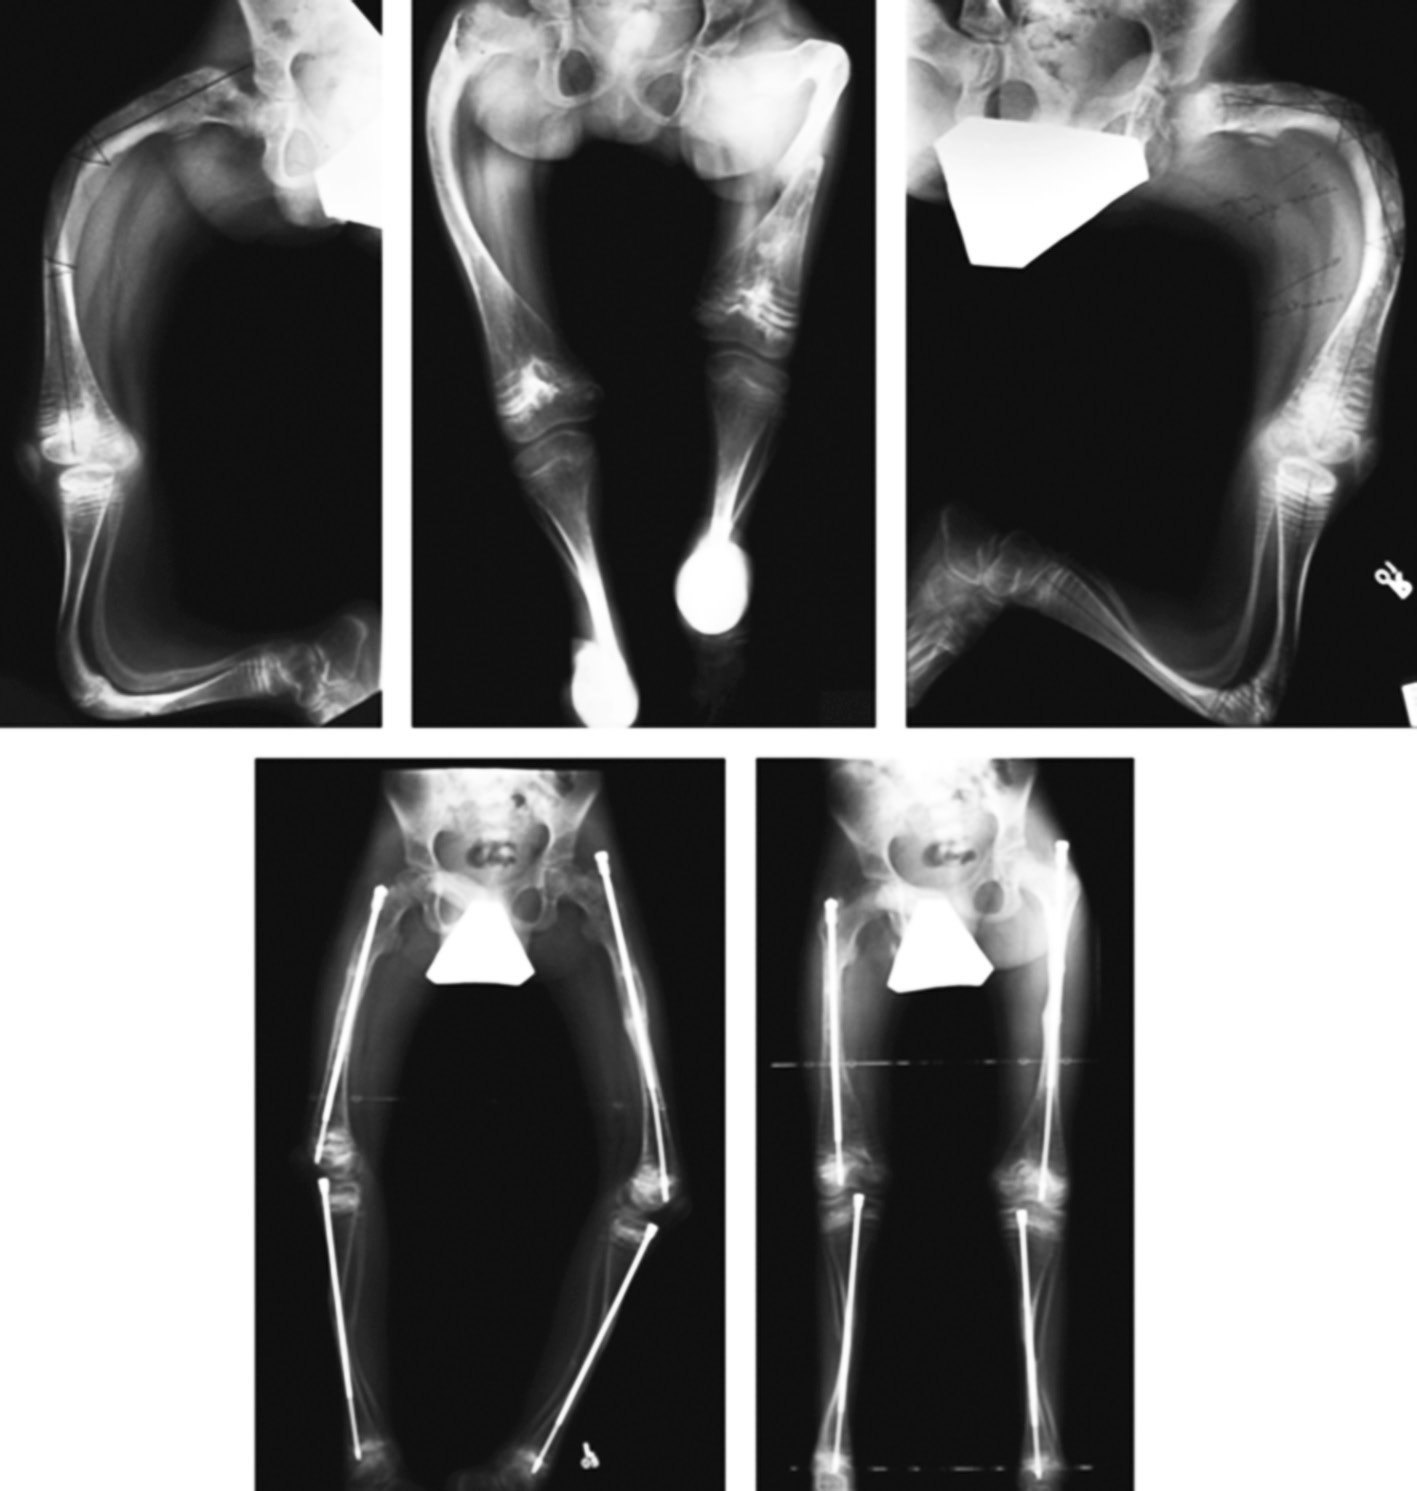

Soft tissues play a key role in the formation of arcuate deformations of long tubular bones. The flexor muscles prevent the bone growth that results in deformity. This is due to the popliteal flexor in the femoral region that leads to anterolateral bending of the bone. This function is performed by the gastrocnemius and fibular muscles in the leg region that cause anteromedial curvature (Fig. 3). Deformed lower limbs lose their biomechanical strength, resulting in increased strain in the deformation apex area that leads to deformation progression and fracture at its height. The purpose of congenital and post-traumatic deformities correction is to reduce the frequency of fractures and ensure the proper growth of the bone to verticalize the child and teach him to walk.

Fig. 3. Deformations of the lower extremities with osteogenesis imperfecta

In 1952, Sofield and Millar first described the technique of multiple osteotomies followed by the installation of an intramedullary rod [55]. However, the fixator ceased to overlap the entire length of the bone during the bone growth process, causing recurrent deformities and reimplant fractures requiring repeated surgery. In 1963, Bailey and Dubow first proposed the telescopic intramedullary system, which lengthened with bone growth [56]. However, the frequency of complications remained high. This was due to the lack of this fixator–the screwed-in T-shaped tip often migrated into the soft tissues (Fig. 5, g). In a modified version of this rod (Sheffield rod), the tip was fixed to the rods, and the problem was solved (Fig. 5, a) [51]. Installing such rods required the arthrotomy of adjacent joints that were especially traumatic when fixing the tibia. Fassier and Duval developed a telescopic rod with a mini-invasive antegrade injection, which significantly reduced the incidence of trauma intraoperatively (Fig. 4) [57]. The threaded part of the solid rod was fixed in the distal epiphysis. Сho et al. proposed their own version of distal fixation. A solid part of the structure had a xiphoid tip with a hole, through which blocking by threaded rod was performed in the epiphysis [58]. The osteotomy technique was also improved. Li et al. suggested mini-invasive osteotomy to preserve periosteal blood circulation and reduce intraoperative blood loss [59].

Fig. 4. Correction of multiplaned deformities of the lower extremities, intramedullary fixation with a Fassier–Duval rod [57]